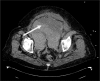

An elderly patient, who was being treated for therapeutic enoxaparin for a couple of days due to suspected deep vein thrombosis, was admitted to hospital following a collapse and severe abdominal pain. She was in hypovolemic shock and was fluid resuscitated. Ultrasound scan and computed tomography (CT) scan showed a large pelvic hematoma. Radiologists also suspected a possibility of bleeding from inferior epigastric artery following a CT angiogram. The patient was stabilized and transferred to intensive care unit (ICU) for further hemodynamic supports and close monitoring. The patient was then transferred back to the general ward when she was stable. She was managed conservatively as there were no more signs of active bleeding. Unfortunately, she died of recurrent bleeding three days after ICU discharge.